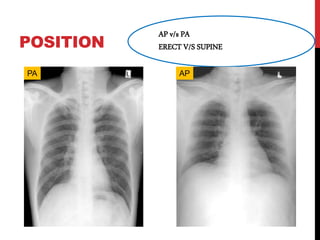

POSITION

AP v/s PA

ERECT V/S SUPINE

PA AP

POSITION AP v/s PA ERECTV/S SUPINE PA AP